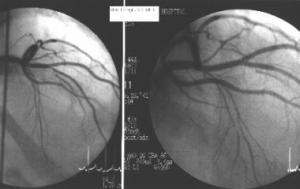

Coronary artery atherosclerosis is the single largest killer of men and women in the United States.

CT scanning accurately demonstrates dilation of the aorta and involvement of major branch vessels proximally and distally. This information helps in determining the appropriate intervention, which may be either surgical or endovascular repair. (See the image below.)